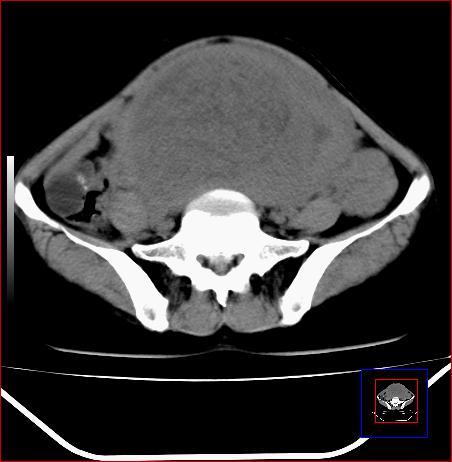

标题: CT15141:子宫肌瘤还是卵巢肿瘤 [打印本页]

标题: CT15141:子宫肌瘤还是卵巢肿瘤

腹部包块1年余,近两月明显增大,月经量多

子宫体积增大,内密度不均匀。边缘清晰。考虑子宫肌瘤。

病灶呈实性包块,边界清晰,似与子宫分界不清,考虑:子宫肌瘤可能性大。其他待排

考虑子宫腺肌症;不排除子宫肌瘤。

子宫体积增大,内密度不均匀。边缘清晰。考虑子宫肌瘤可能性大。